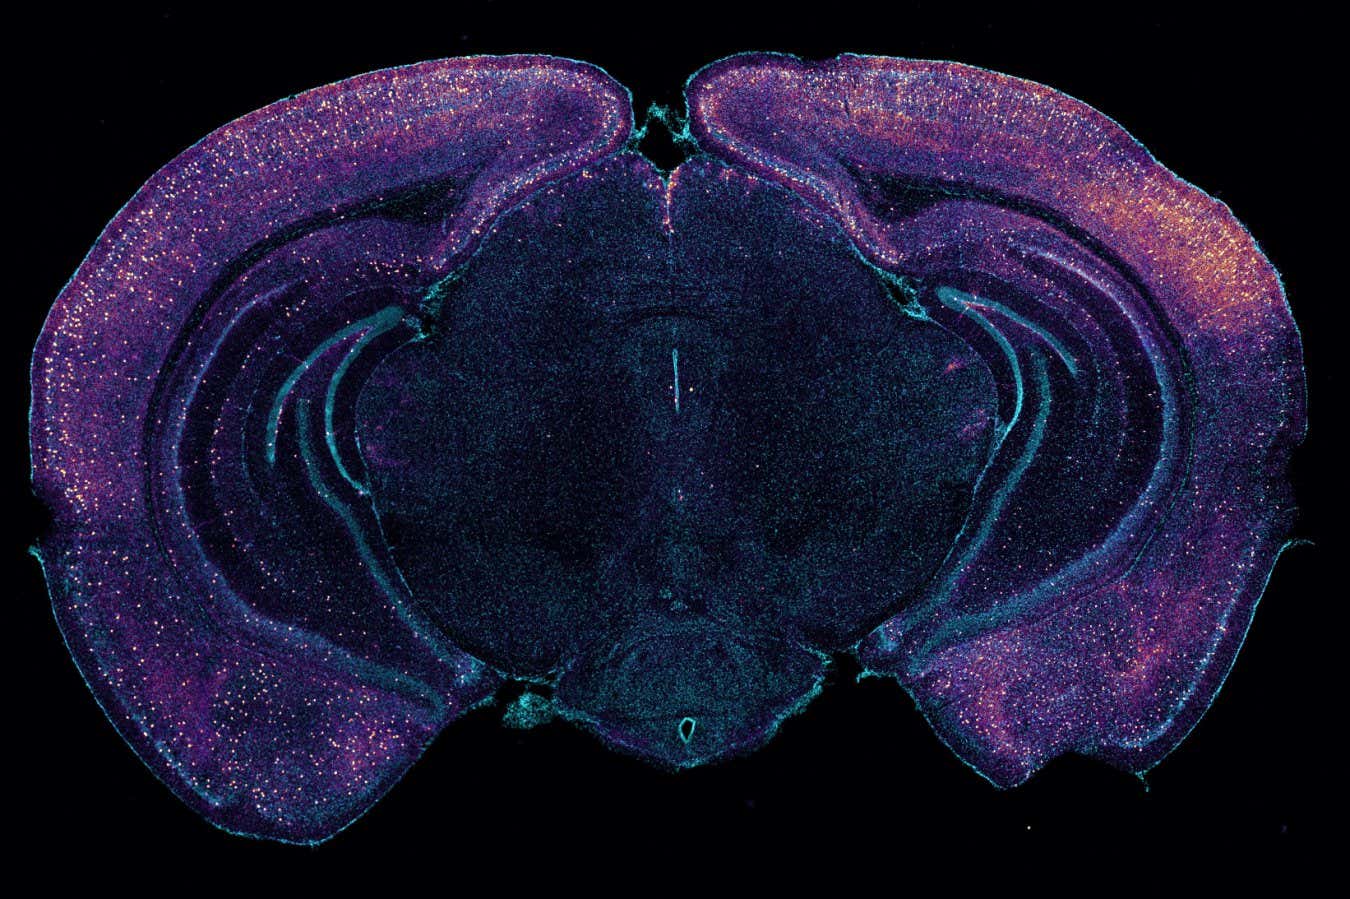

Cross-section of a mouse brain highlighting neurons that appear to release molecules that increase toxin clearance

Tsai Laboratory/MIT Picower Laboratory

The research team also found that the activity of a particular type of brain cell known as an interneuron appears to cause an increase in glymph flow by releasing a molecule called vasoactive intestinal peptide. When the research team chemically blocked the production of this molecule, the treatment no longer accelerated amyloid clearance.